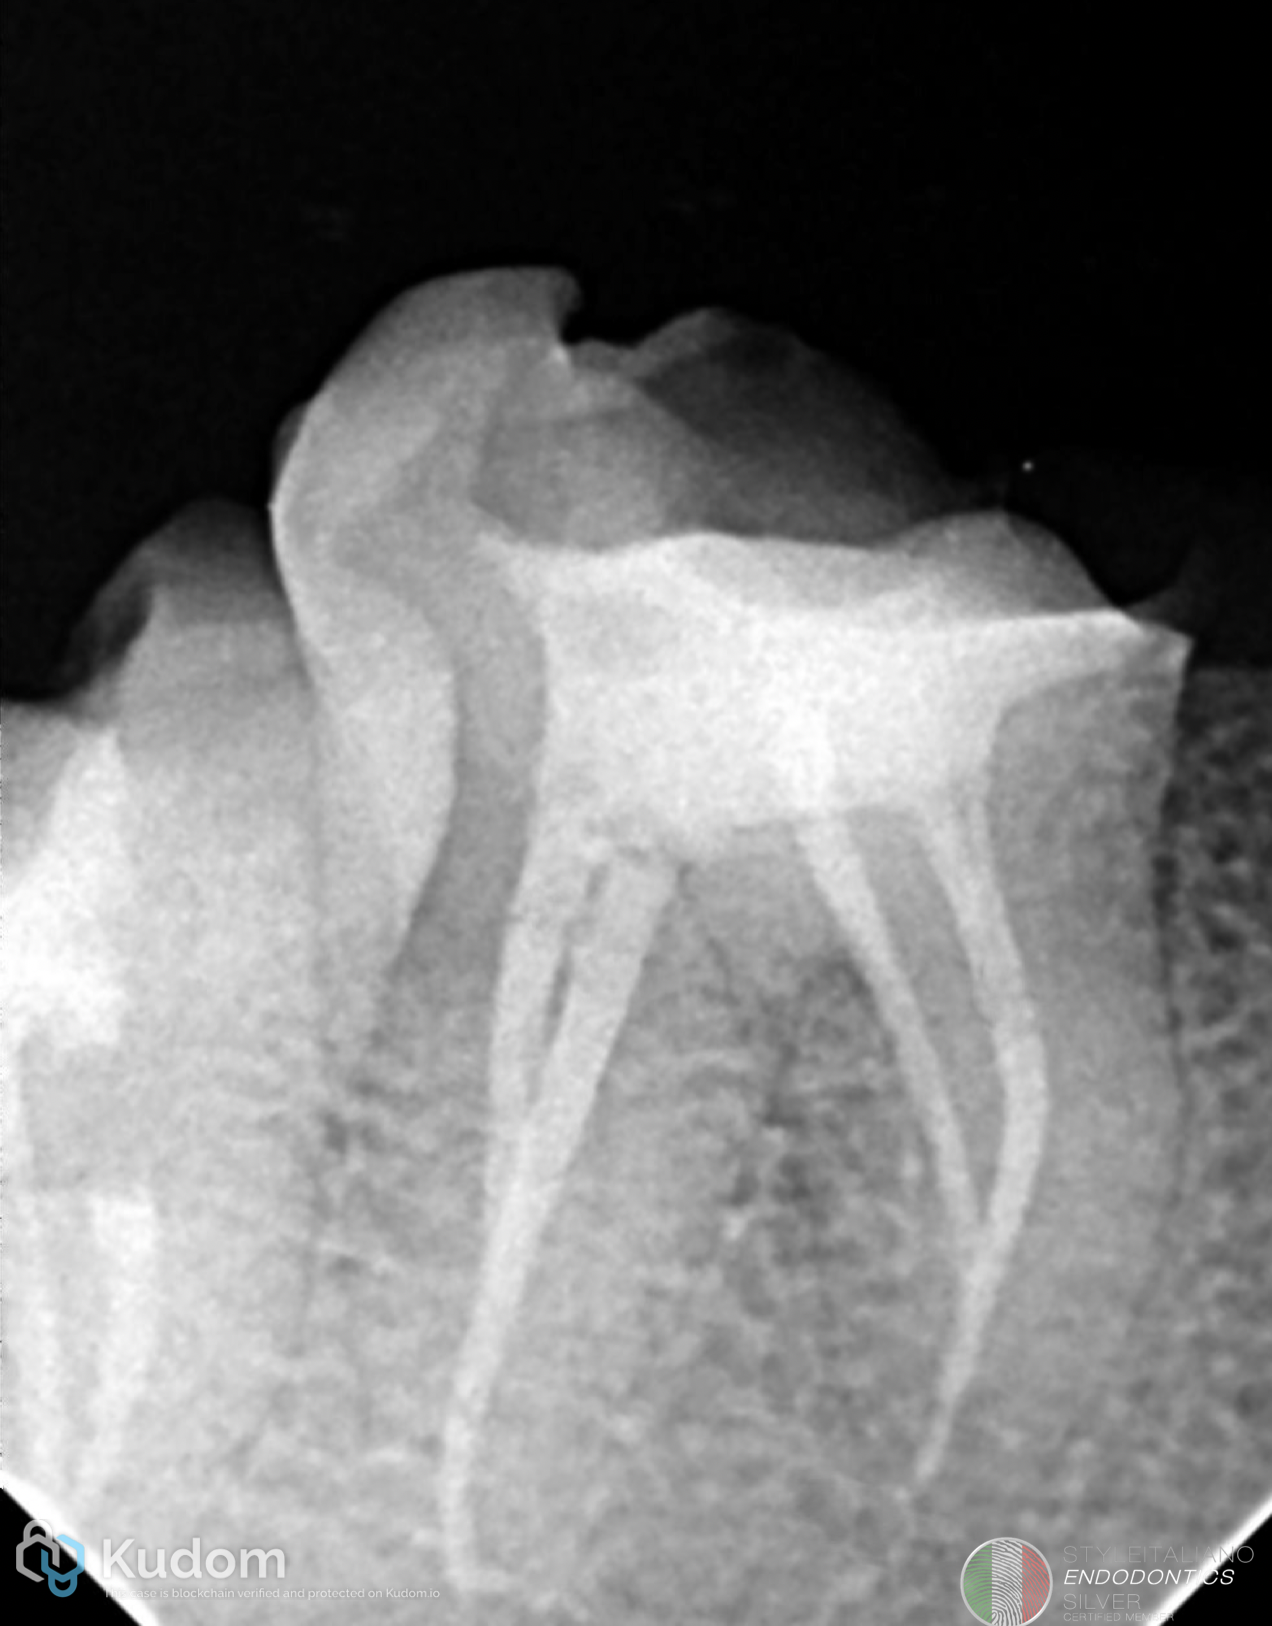

Fig. 4

In this clinical case, shaping was preformed following a modern minimally invasive philosophy, aiming to preserve dentin while achieving adequate mechanical preparation.

The mesial canals were prepared up to size 20/.04 , while the distal system demonstrated.

The distal canal was enlarged up to 25/.04, in accordance with its degree of calcification and original morphology.

Notably, no pre-flaring was performed in selected segments , in order to preserve the peri-cervical dentin (PCD) and avoid unnecessary structural compromise. This reflects strict adherence to minimally invasive principles, where every micron of dentin is respected.

Such an approach particularly when executed in manual less manner demands a high level of expertise and refined kinematic execution.